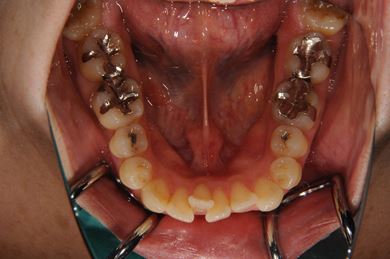

全顎矯正治療+セラミック治療

| 主訴 | 出っ歯 上顎前歯の並び | ||||||||||||||||||||||||||||||||

| 治療方針 | 上下歯牙がだいぶ前にでていて口が閉じづらい状態でした。なるべく金属が入っている歯を抜歯したいので、上下左右第二小臼歯を抜歯して、その隙間を利用して、口元をさげていきました。また、口元を最善の状態にうるために、抜歯スペースを使用したあと、上下左右のインプラントアンカー(釘)でより一層口元を後ろにさげていきました。ただの抜歯ケースよりだいぶ口元が下がっているのが分かります。抜歯したスペースががたつき(叢生量)で使用してしまう場合には、このような方法でより口元をさげることができます。お顔立ちがとてもよくなりました。とても協力していただけたので、しっかりと良くなることができました。 | ||||||||||||||||||||||||||||||||

| 治療内容 | 唇側矯正(ホワイト・上下左右第二小臼歯抜歯・上下インプラントアンカー)、オールセラミッククラウン1本(オールセラミック用土台1本)、ジルコニアフレームオールセラミッククラウン1本 | ||||||||||||||||||||||||||||||||